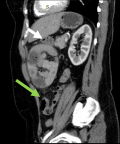

Diagnostic assessment: i) X-ray: plain abdominal radiography demonstrated small bowel air-fluid levels predominantly in the right mesogastric region, without pneumoperitoneum (Figure 1); ii) computed tomography (CT) scan: contrast-enhanced CT confirmed small bowel obstruction due to an internal hernia, with features suggestive of a right paraduodenal hernia (Figure 2-5); iii) laboratory tests: laboratory tests showed leukocytosis with a white blood cell (WBC) count of 12,400/mm3, while liver and kidney function tests, pancreatic enzymes, ionogram, C-reactive protein (CRP), and coagulation profile were all normal.

Figure 3: sagittal reformat images shows inferiorly displaced transverse colon and hepatic flexure of the colon (green arrow)